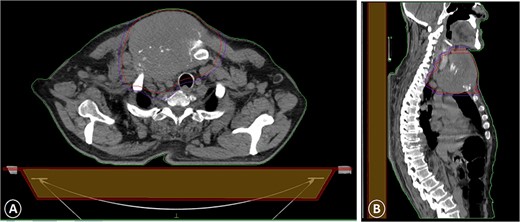

A CT scan with intravenous contrast that showed a sternal tumor of 11 by 12 cm: (A) transversal plane and (B) sagittal plane.

The patient was diagnosed with stage 3 colon cancer, and the standard of care to be given adjuvant chemotherapy was FOLFOX (leucovorin calcium, fluorouracil, and oxaliplatin) or XELOX (capecitabine ‘Xeloda’ and oxaliplatin). However, the patient has maintained on adjuvant therapy XELODA alone due to its poor performance status with comorbidities. During follow-up after the third cycle of adjuvant XELODA chemotherapy, the patient came with a rapidly enlarging, painful, hard mass on the upper part of his sternum over the last month (Fig. 2). A biopsy of the sternum confirmed metastatic adenocarcinoma consistent with the known primary colon cancer. A CT simulation was done and demonstrated a single destructive lesion in the sternum (Fig. 3). The patient received external beam radiotherapy (EBRT) to the sternum, consisting of 30 Gy delivered in 10 fractions, resulting in symptomatic improvement and a reduction in mass size post-treatment (Fig. 4). The patient was evaluated 3 months after finishing radiotherapy, with a good general condition and resolution of the sternal mass, and he is on a regular follow-up in the radiation oncology clinic.